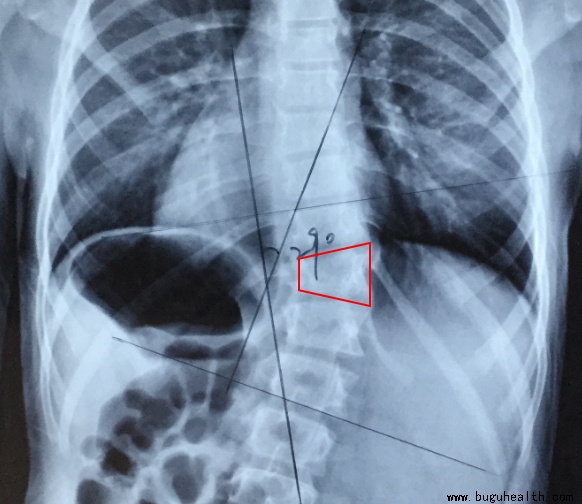

以下患儿,虽然已经穿戴支具3年,但因骨骼生长没有闭合,且仍然有残存度数,所以,需要继续穿戴。

脊柱侧弯